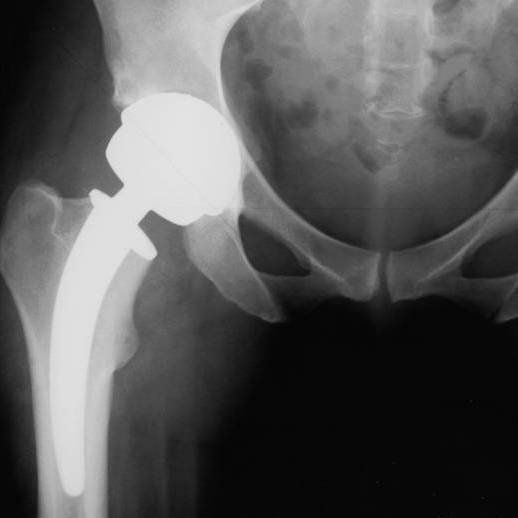

Stellungnahme der Deutschen Gesellschaft für Orthopädie und orthopädische Chirurgie (DGOOC)

Metall-Auf Metall-Hüftendoprothesen